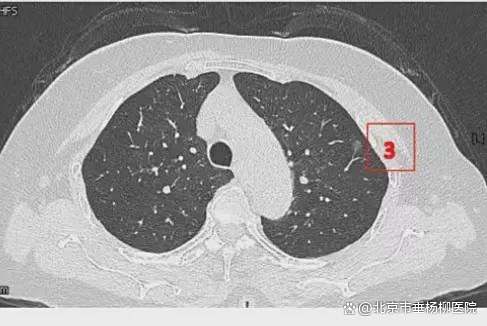

患者女性,71岁,因“发现左肺多发结节2周”入院。胸部CT提示左肺多发磨玻璃结节,较大者位于左肺上叶,呈类圆形,边界清晰,最大直径约9mm。该CT表现高度提示恶性可能。鉴于患者结节数量较多,为减少术中肺组织损伤,术前于CT引导下行经皮肺结节定位术,继而实施胸腔镜下左肺楔形切除术。术中共切除肺部结节6枚。术后病理示:左肺上叶较大结节(4号)为微浸润腺癌,其余5枚结节均为原位癌。患者术后恢复良好,于术后第1天拔除胸腔引流管,第4天顺利出院。

影像资料